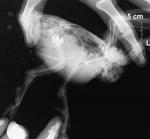

Голубь, переломы лап.

post-46676-1382625560_thumb.jpg

Снимок лап

post-46676-1382625655_thumb.jpg

Фото некроза лапы

Снимок лап. При осмотре до рентгена были предположены переломы обеих лап, что и подтвердил рентген. Открытый перелом правой голени, дистальной части и закрытый перелом левой цевки. Увы, ветеринаром были сделаны две грубых ошибки. Было неверно оценено состояние правой лапы - она была зафиксирована шиной, тогда как ее, буквально "болтающуюся на коже", надо было ампутировать - в результате возникла влажная гангрена (фото справа) и был неверно назначен антибиотик - гентамицин перорально, тогда как он в ЖКТ практически не всасывается, надо было либо его же, но парентерально, либо если уж перорально, то что-то из пенициллиновой или цефалоспориновой групп. В итоге, позже лапа была ампутирована, но вскоре птица погибла от септицемии.